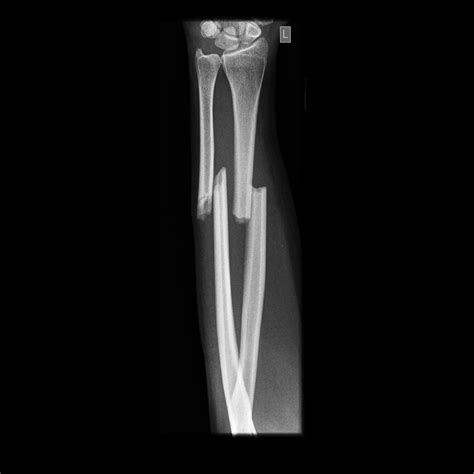

• X-Rays: X-rays are the primary imaging tool used to confirm the presence and severity of a fracture. They provide detailed images of the bones and can show the exact location and type of fracture.